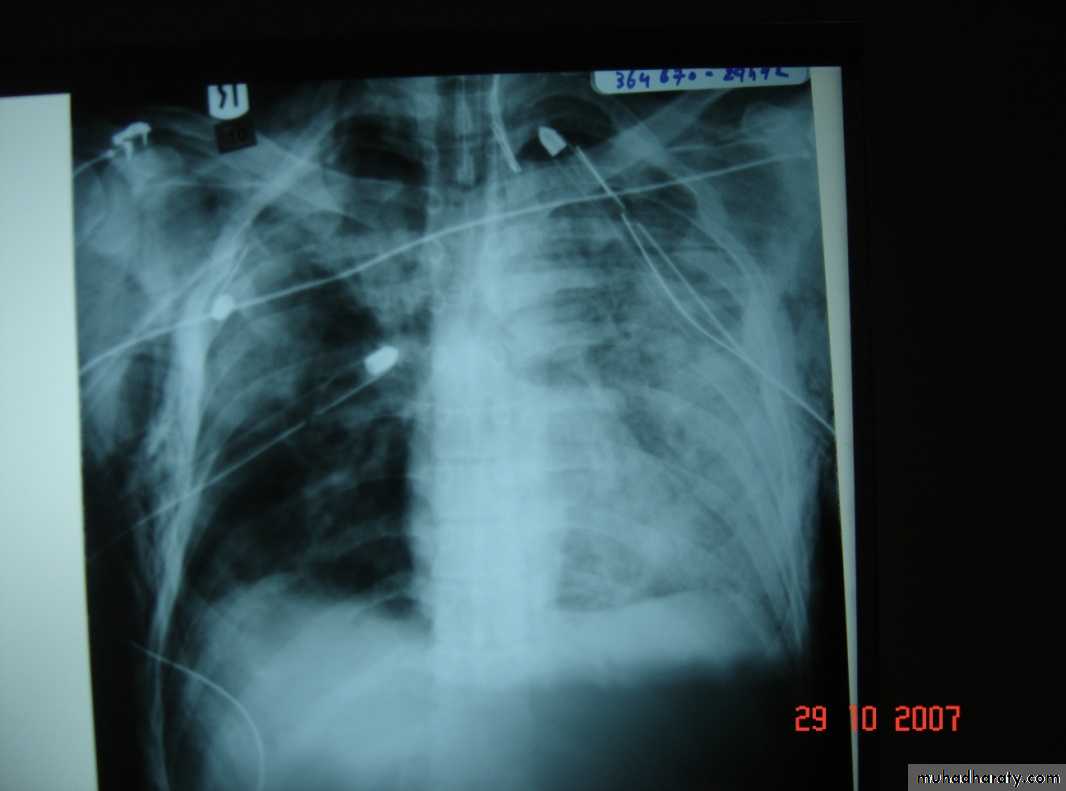

• 3-Pleurl injuries Can lead toA-Pneumothorax which can be partial or complete closed or open sucking or tension pnemothorax . B-Haemothorax may be mild or severe and may be with pneumothorax

Collapsed lungTraumatic haemothorax

• 4-Pulmonary injuriesTrauma can lead to pulmonary contusion with interstitial edema which may lead to consolidation of the lung tissues and can be manage by antibiotics administration and clearing of secretion

• Complications of chest injuries 1-ARDS: Syndrome of acute RF with the formation of a non –cardiogenic pulmonary edema leading to reduced lung compliance and hypoxaemia which is refractory to oxygen therapy characterized by bilateral diffuse pulmonary infiltrate on chest X-ray (white lung) .A less severe case (ALI=acute lung injury ) which consists of a non specific pathological changes in the lung in response to a specific insult . 2-Atelectasis3-Infection4-Pulmonary embolism5-Air embolism6-Traecheal complications7-Cardiac arrhythmias